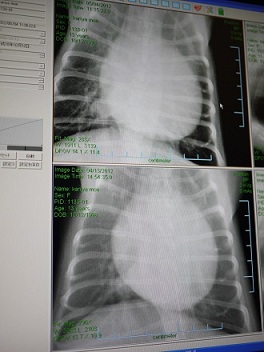

ガァガァ咳が呼吸器からくるものか、

循環器からなのかの咳かの判断で必要だったんだと思います。

上が今日のレントゲンで、下は初診の時のもの。

透明度も違いますけど、気持ち、大きさが少し小さくなったように思います。

横向き。

今日はレントゲンから診る 心臓の大きさ?の測り方も教えてもらいました。

Vertebra Heart Scale (V.H.S)と言うそうです。

脊椎 心臓 大きさ

心臓のエコーで、こんなふーに測るのは知ってたけど レントゲンにもあるんだね。

先生も、がっちり正確な数値じゃないんだけどね。って言ってた。

初診の時は11.6 → 今日は11.1 (8.5~10.5が正常値)

僅か5mmだけど、レントゲンで5mmって凄くない!?('∇'*)